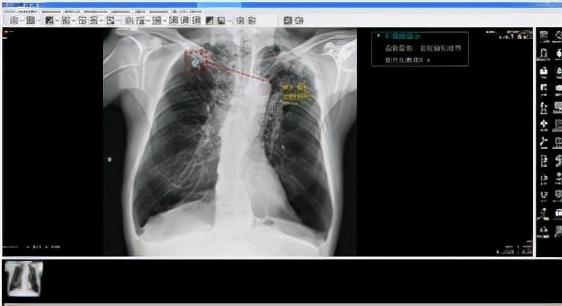

为此,天地智慧医疗专门开发了——全链AI胸部影像智能分析系统,影像科医生通过全链AI服务可以辅助医生使用云PACS进行影像快速筛查,大幅提升医生诊断效率。全链AI胸部影像智能分析系统包含采集控制AI、影像分析AI、阅片诊断AI、科室管理AI等,辅助医生从拍摄到诊断的影像全流程。

尤其在胸部正位常见疾病AI辅助诊断有着高于同行业的诊断准确率。天医云全链AI,针对体检中常见的十四种胸部肺部疾病(包括肺结节、肺水肿、肺不张、肺实变、气胸、肺炎等)及职业病(肺结核、尘肺矽病等)最高可实现诊断准确率(AUC)92.6%、灵敏度96.2%和特异性85.1%的优异表现,可极大程度有效提升胸部X-射线影像检查效率和诊断质量。

全链AI胸部影像智能分析系统基于基于计算机视觉算法、大数据训练、神经网络的深度学习,将AI融入到放射医学影像全流程中,实现智能检索,海量筛查以及精确诊断,为临床提供更高质量超清影像,并以一致客观的量化标准实现自动化测量、批量数据准确筛查和多类型病灶智能提示功能,有效提升临床诊断质量、效率和收益,强化体检中心在同等规模体检中心的竞争力,减低阅片医生工作负担并优化患者就诊体验。